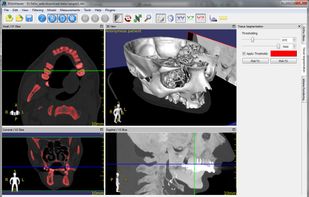

Weasis is a multipurpose standalone and web-based DICOM viewer with a highly modular architecture. It is a very popular clinical viewer used in healthcare by hospitals, health networks, multicenter research trials, and patients.

Weasis is a multipurpose standalone and web-based DICOM viewer with a highly modular architecture. It is a very popular clinical viewer used in healthcare by hospitals, health networks, multicenter research trials, and patients.